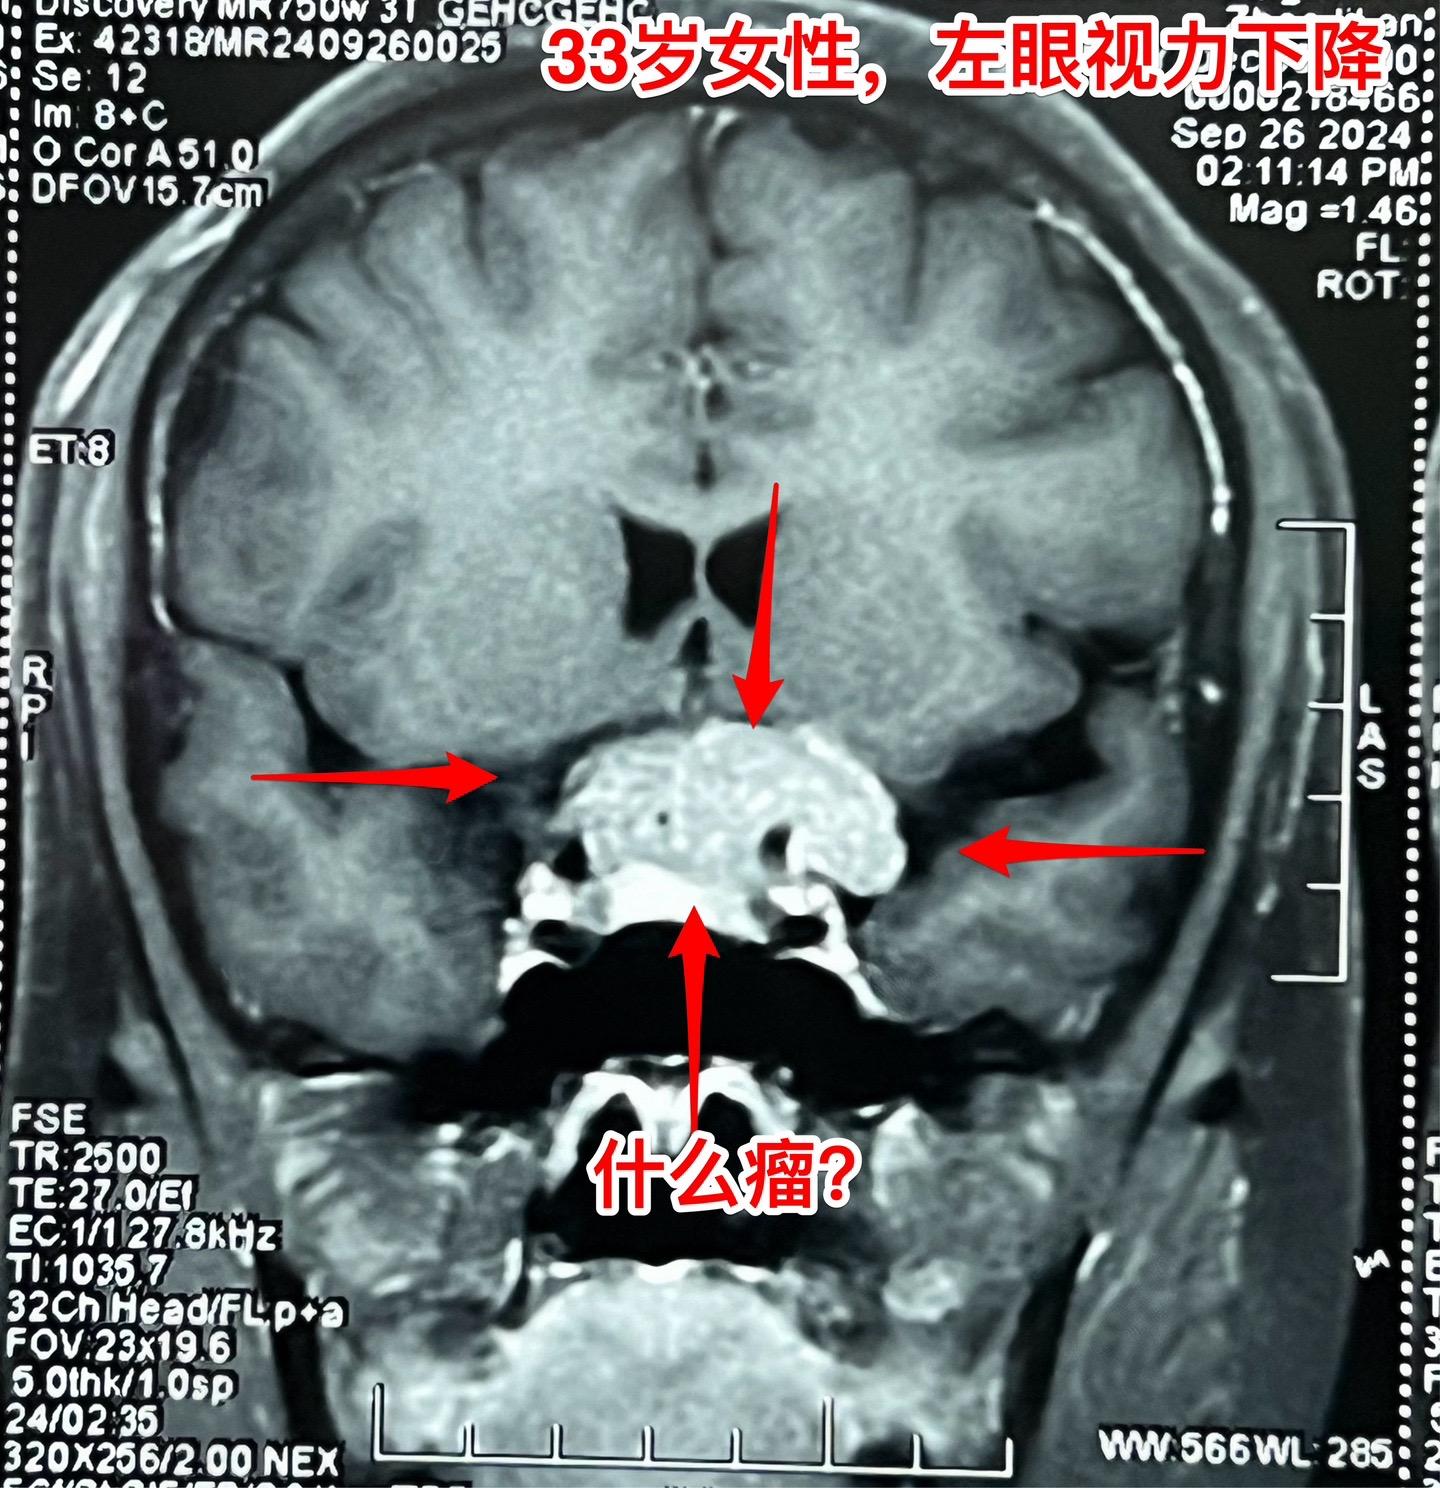

国庆节长假后第一天完成两个手术。一个手是33岁女性,来自云南省香格里拉。因左眼视力下降,到医院检查发现鞍区肿瘤,怀疑是颅咽管瘤。病人没有内分泌功能障碍。影像学上肿瘤是实性的,没有钙化,而且可以看见垂体信号。到底是什么肿瘤呢?今天手术中取肿瘤标本作快速冰冻病理检查,报告是垂体瘤。肿瘤得到完全切除,手术后病人视力好转了。 另一个手术是11岁男孩子,颅咽管瘤复发。经原切口翼点入路将肿瘤完全切除。术前磁共振只看见一个圆形肿瘤,术中发现除了这个肿瘤外还有5个散在的钙化斑,均得到完全切除。这样的散在钙化斑是潜在的危险因